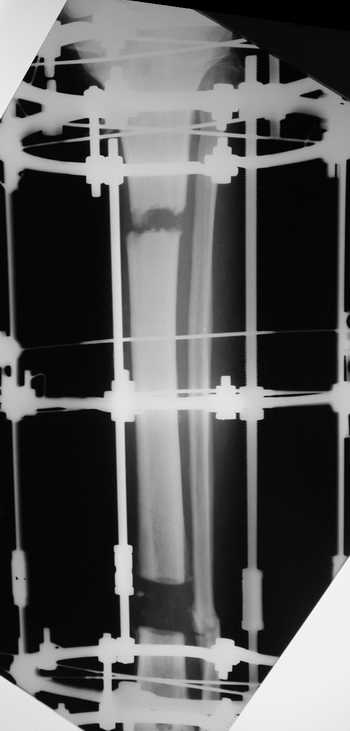

остеотомия м\б кости, аппарат Илизарова. По рентгенограммам в двух проекциях произведено планирование устранения смещений (рис 2 и 3), между вторым и третьим кольцом установлены 6 телескопических дистракторов Гесапода, данные введены в программу, и далее втечение 10 дней больная подкручивала телескопы согласно выданной компьютером инструкции. По завершению репозиции гексаподные телескопы обратно заменены на обычные штанги от аппарата Илизарова (рис 4 и 5). Еще через две недели забит гвоздь (рис 6, контроль

через 4 месяца).